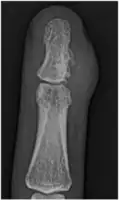

A well-defined area of bone loss in the medulla of the bone is seen on x-ray.[2]

X-Ray right middle finger: juxta-cortical chondroma